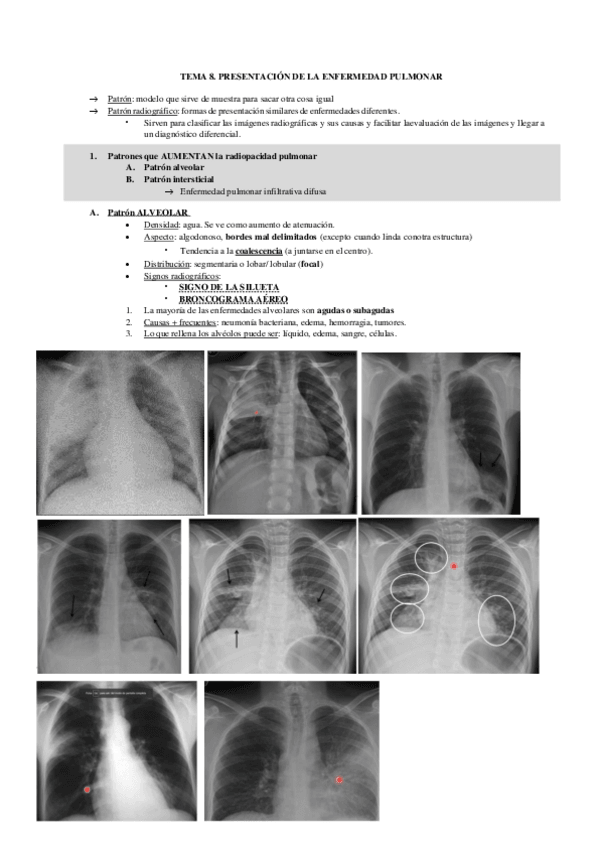

TEMA-8.pdf